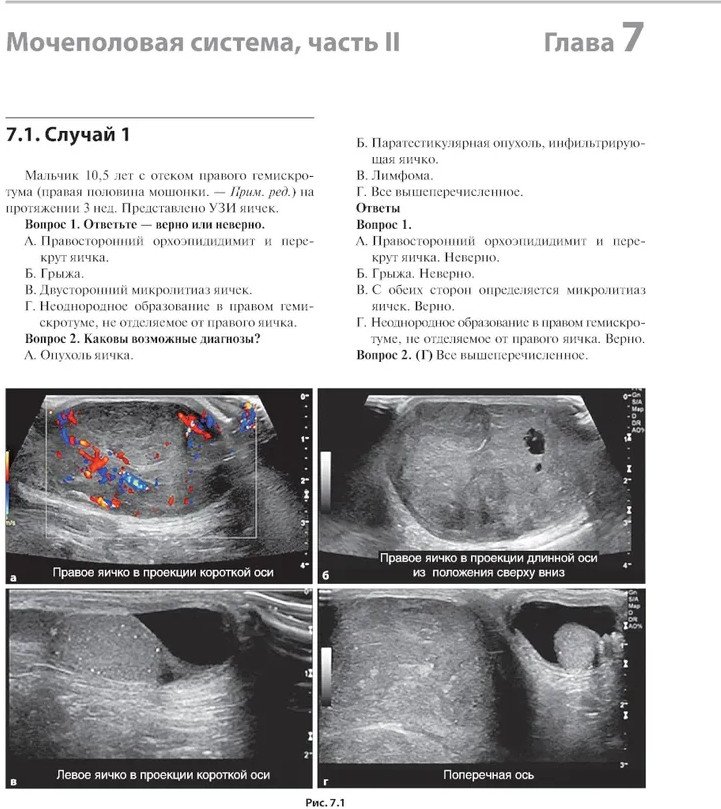

💳 Оплатить за товар можно при получении 🇰🇿 Есть бесплатная доставка по Казахстану 🎁 Копите бонусы с каждой покупки В книге рассмотрены сложные клинические радиологические случаи, охватывающие патологию центральной нервной системы, дыхательной и сердечно-сосудистой систем, желудочно-кишечного тракта, мочеполовой системы и опорно-двигательного аппарата в педиатрической практике. Случаи представлены с соответствующей историей болезни и подходящими изображениями исследований, за которыми следует обсуждение рентгенологических заключений при использовании различных методов лучевой диагностики. Также, в конце описания каждого случая выделены ключевые моменты, которые необходимо запомнить. Книга объединяет опыт врачей-рентгенологов и клинических ординаторов и представляет актуальную учебную информацию, способствующую улучшению качества оказания медицинской помощи. |